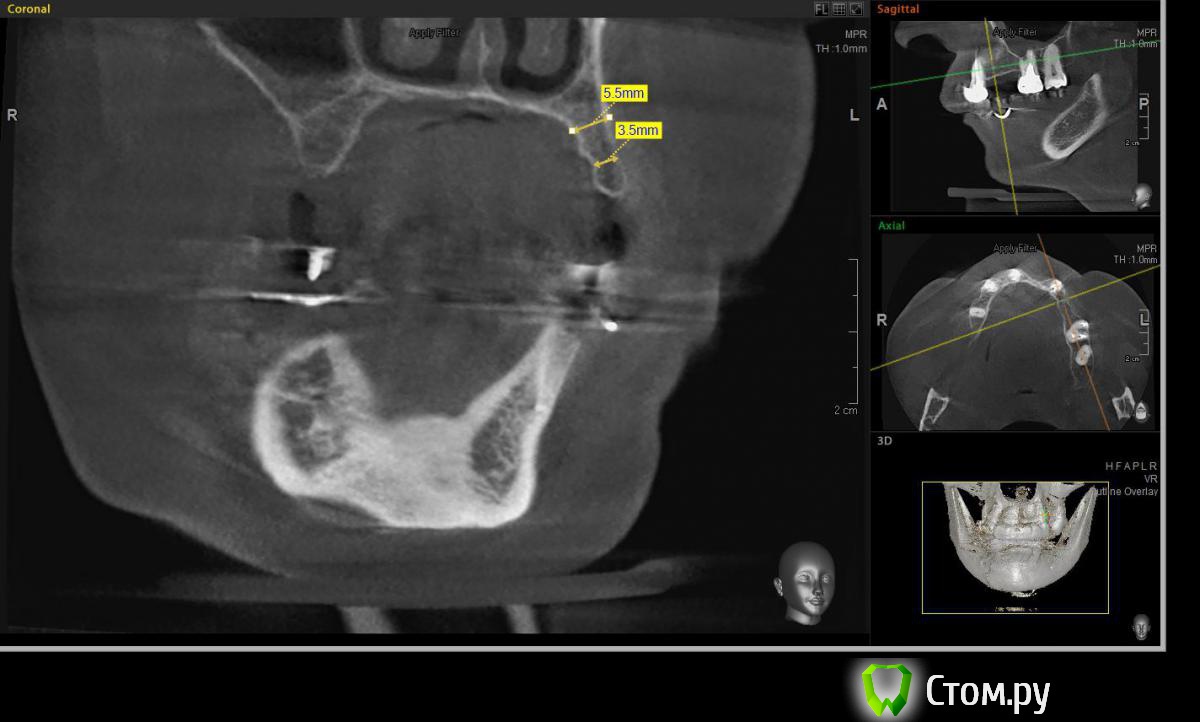

Евгений Ходыкин Опубликовано 23 июля, 2014 Поделиться Опубликовано 23 июля, 2014 Решили с пациенткой пока начать с в.ч. В планах имплантация в область отсутствующих 1.6, 1.4, 1.2, 2.1, 2.2, 2.4, 2.5. С 1.6 самому более менее все понятно, мануальных навыков хватит) Прошу помощи коллег относительно остальных областей. Фронт особливо печален... Забегая наперед скажу, что блоки еще не делал. Ауто точно пока брать не планирую, ибо нет даже теоретических навыков. Хочу начать все-таки с аллоблоков. У кого какие будут мнения, заранее спасибо) Ссылка на комментарий

Евгений Ходыкин Опубликовано 24 июля, 2014 Автор Поделиться Опубликовано 24 июля, 2014 В области 2.4 выраженная нёбная резорбция. Крепить мембрану туда, или все-равно наращивать вестибулярно?? Ссылка на комментарий